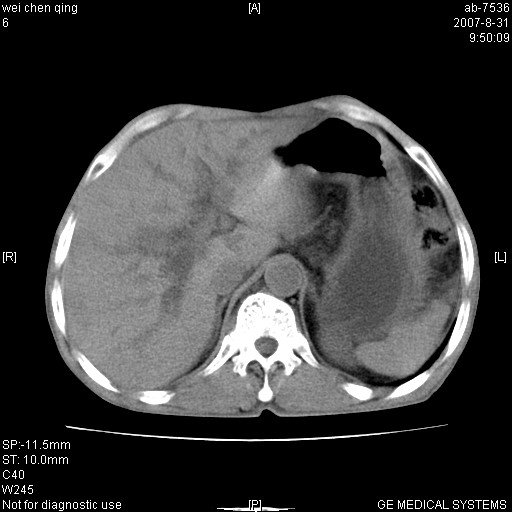

以下是引用zyyzzy在2007-8-31 14:34:00的发言:[br]该病人肝内胆管扩张,胆囊及胆总管未见明显扩张。在倒数第9层图像上可看到左右肝管结合部(肝总管)有软组织影,此处应薄层扫描。考虑肝总管占位(ca)、腹水。[br]